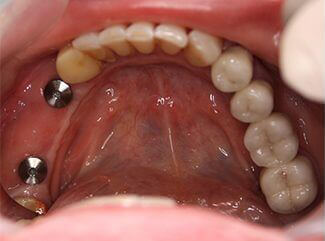

Probleem. Mitmekordsed karioossed kahjustused hammastel, suur hammaste väärarengute tase.

Lahendus. Halva hambaprognoosi tõttu eemaldati ülejäänud hambad ja paigaldati neli hambaimplantaati ülemisse ja alumisse lõualuusse. Implantaadid toetati metallist keraamiliste kroonidega.